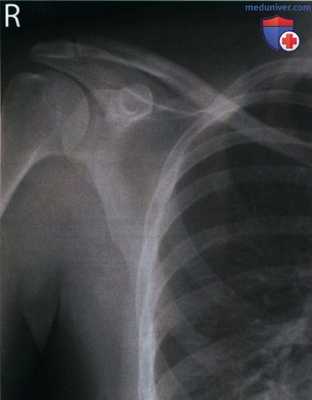

РИСУНОК 1 Рентгенограмма лопатки в ПЗ проекции: правильное положение.

• Передний и задний края суставной впадины лопатки почти накладываются друг на друга

• Грудная полость накладывается на позвоночный край лопатки, а не на ее латеральный край

• Отсутствует наложение ключицы на верхний угол лопатки

• Диафиз плечевой кости отведен на 90° (рис. 3 и 4)

• Отсутствует продольное проекционное укорочение лопатки

• Верхний угол лопатки визуализируется чуть ниже ключицы (на 0,6 см)

• Середина тела лопатки находится в центре экспозиционного поля

• В экспозиционное поле входит лопатка

• Структуры лопатки, накладывающиеся на грудную клетку, характеризуются приемлемым контрастным разрешением

а) Анализ. Нижнелатеральный край лопатки накладывается на грудную полость, верхний угол лопатки накладывается на ключицу. Плечевая кость была отведена недостаточно.

б) Коррекция. Отведите плечевую кость на 90° относительно туловища.